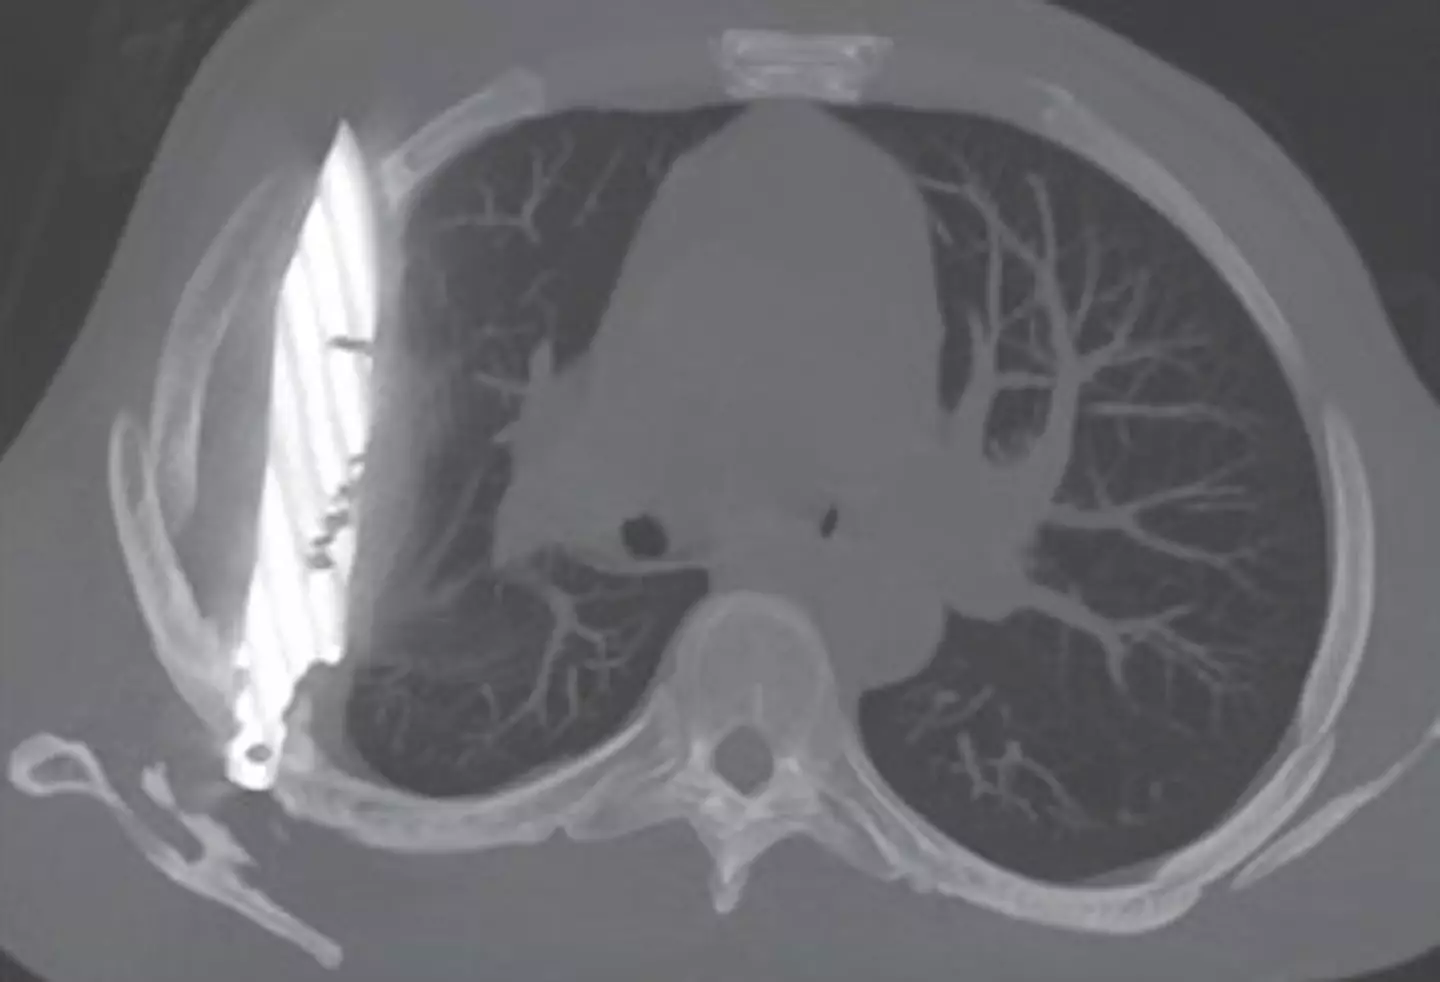

Sometimes truth is stranger than fiction, after an X-ray revealed the man had a sizeable knife buried deep inside his chest.

After ordering an X-ray, a 'retained metallic object' was found, and medics realised it was a knife, and it was surrounded by 'pus and necrotic tissue'.

It had entered his body through his right shoulder.